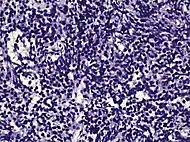

| Acinar adenocarcinoma - 93%[2] | Adenocarcinoma (not otherwise specified/ conventional/ usual acinar)[3] |

77%[notes 2] | 54%[notes 2] | ![]() |

These constitute 93% of prostate cancers.[2]